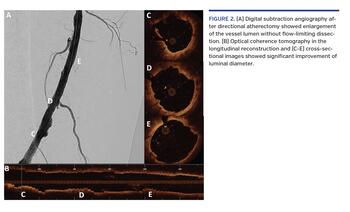

A 70-year-old man presented with lifestyle-limiting intermittent claudication (Rutherford stage III) affecting the right lower extremity. Physical examination of the right lower limb revealed weak distal pulses and a diminished ankle-brachial index of 0.6. Peripheral angiogram showed diffuse 80% stenosis over the right distal superficial femoral artery (SFA).

The HawkOne directional atherectomy system (Medtronic Peripheral) was used to restore blood flow by removing plaque. After placing a 7 mm SpiderFX device (Medtronic Peripheral), optical coherence tomography (OCT) was acquired to assess baseline plaque load (Figure 1). Several runs of directional atherectomy were done. Angiogram and OCT were then obtained to assess the result of directional atherectomy (Figure 2). Drug-eluting balloon was applied afterward. The final angiographic result was excellent. A 3-month course of dual-antiplatelet therapy was given, followed by lifelong aspirin. There was no recurrence of symptoms at subsequent 1-year follow-up.